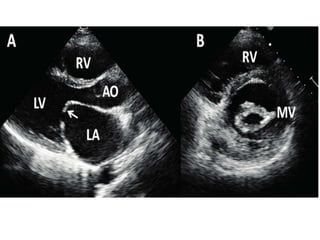

A)Long axis view-both leaflets are thickend with pliable anterior

leaflet

B)Short axis view-fusion of both commissures

C) A coptation defect of mitral can be detected with severely

dilated LA. D) colour flow mapping showing severe MR